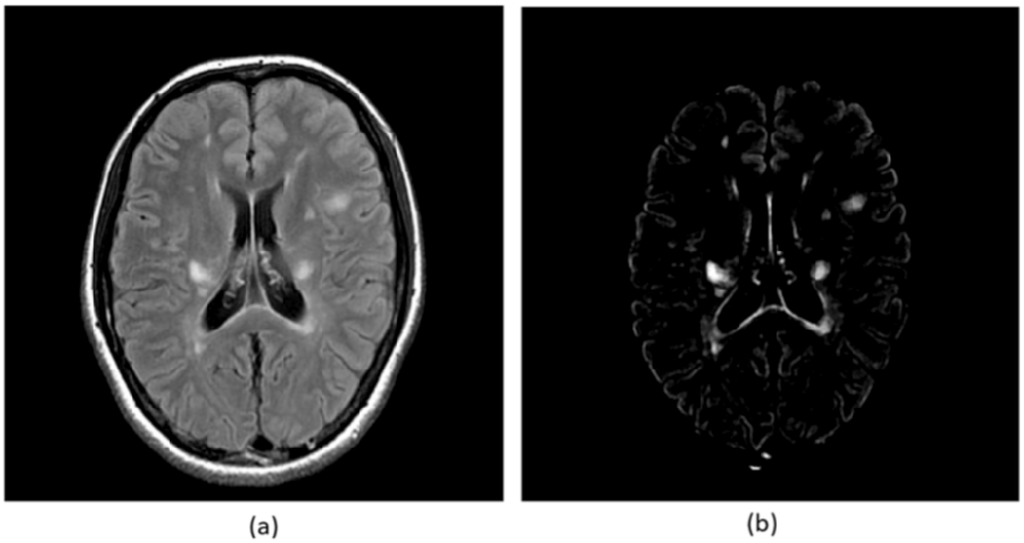

where t is the time and F is the speed function. While updating the level set function, the zero level set ϕ = 0 moves according to the speed function in the higher dimensional level set function. Here, the zero level set is called as “moving front”. Finally, the update of the level set function was stopped if some conditions are satisfied. Figures 7(a) and 7(b) show the illustrations of an original T2-weighted image and white matter regions segmented by a level set method, respectively [55].

Figure 7.

Illustrations of: (a) an original T2-weighted image and (b) white matter regions segmented by a level set method [55].